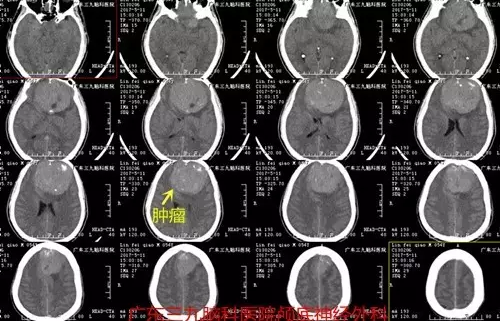

▲术前CT提示额部类圆形稍高密度占位性病变,大小约7.5cm×7.2cm×7.5cm

▲术前CTA提示肿瘤血供极丰富